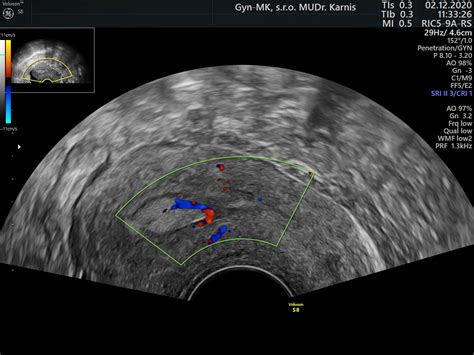

Ultrasound diagnosis of endometrial hyperplasia in postmenopausal women (Ultrazvuková diagnostika hyperplázie endometria u postmenopauzálnych žien) je kľúčová oblasť v gynekológii. Hodnotenie hrúbky endometria, stanovenie fyziologickej hranice a manažment asymptomatických postmenopauzálnych pacientok so zhrubnutým endometriom predstavujú významnú výzvu. Bežne sa stáva, že obvodní gynekológovia odosielajú pacientky s hrúbkou endometria presahujúcou 3-4 mm, ktoré nemajú žiadne klinické prejavy krvácania ani iné patologické symptómy, na kyretáž dutiny maternice s predbežnou diagnózou hyperplázie endometria. Táto diagnóza sa však často pri následnej histologickej verifikácii nepotvrdí.

Manažment týchto skupín pacientok je komplikovaný a mal by byť prispôsobený individuálnym potrebám každej ženy, pričom je nevyhnutné zohľadniť prítomnosť rizikových faktorov a preferencie pacientky. V súčasnosti sa sonografické meranie hrúbky endometria neprezentuje ako vhodná skríningová metóda na detekciu karcinómu endometria.